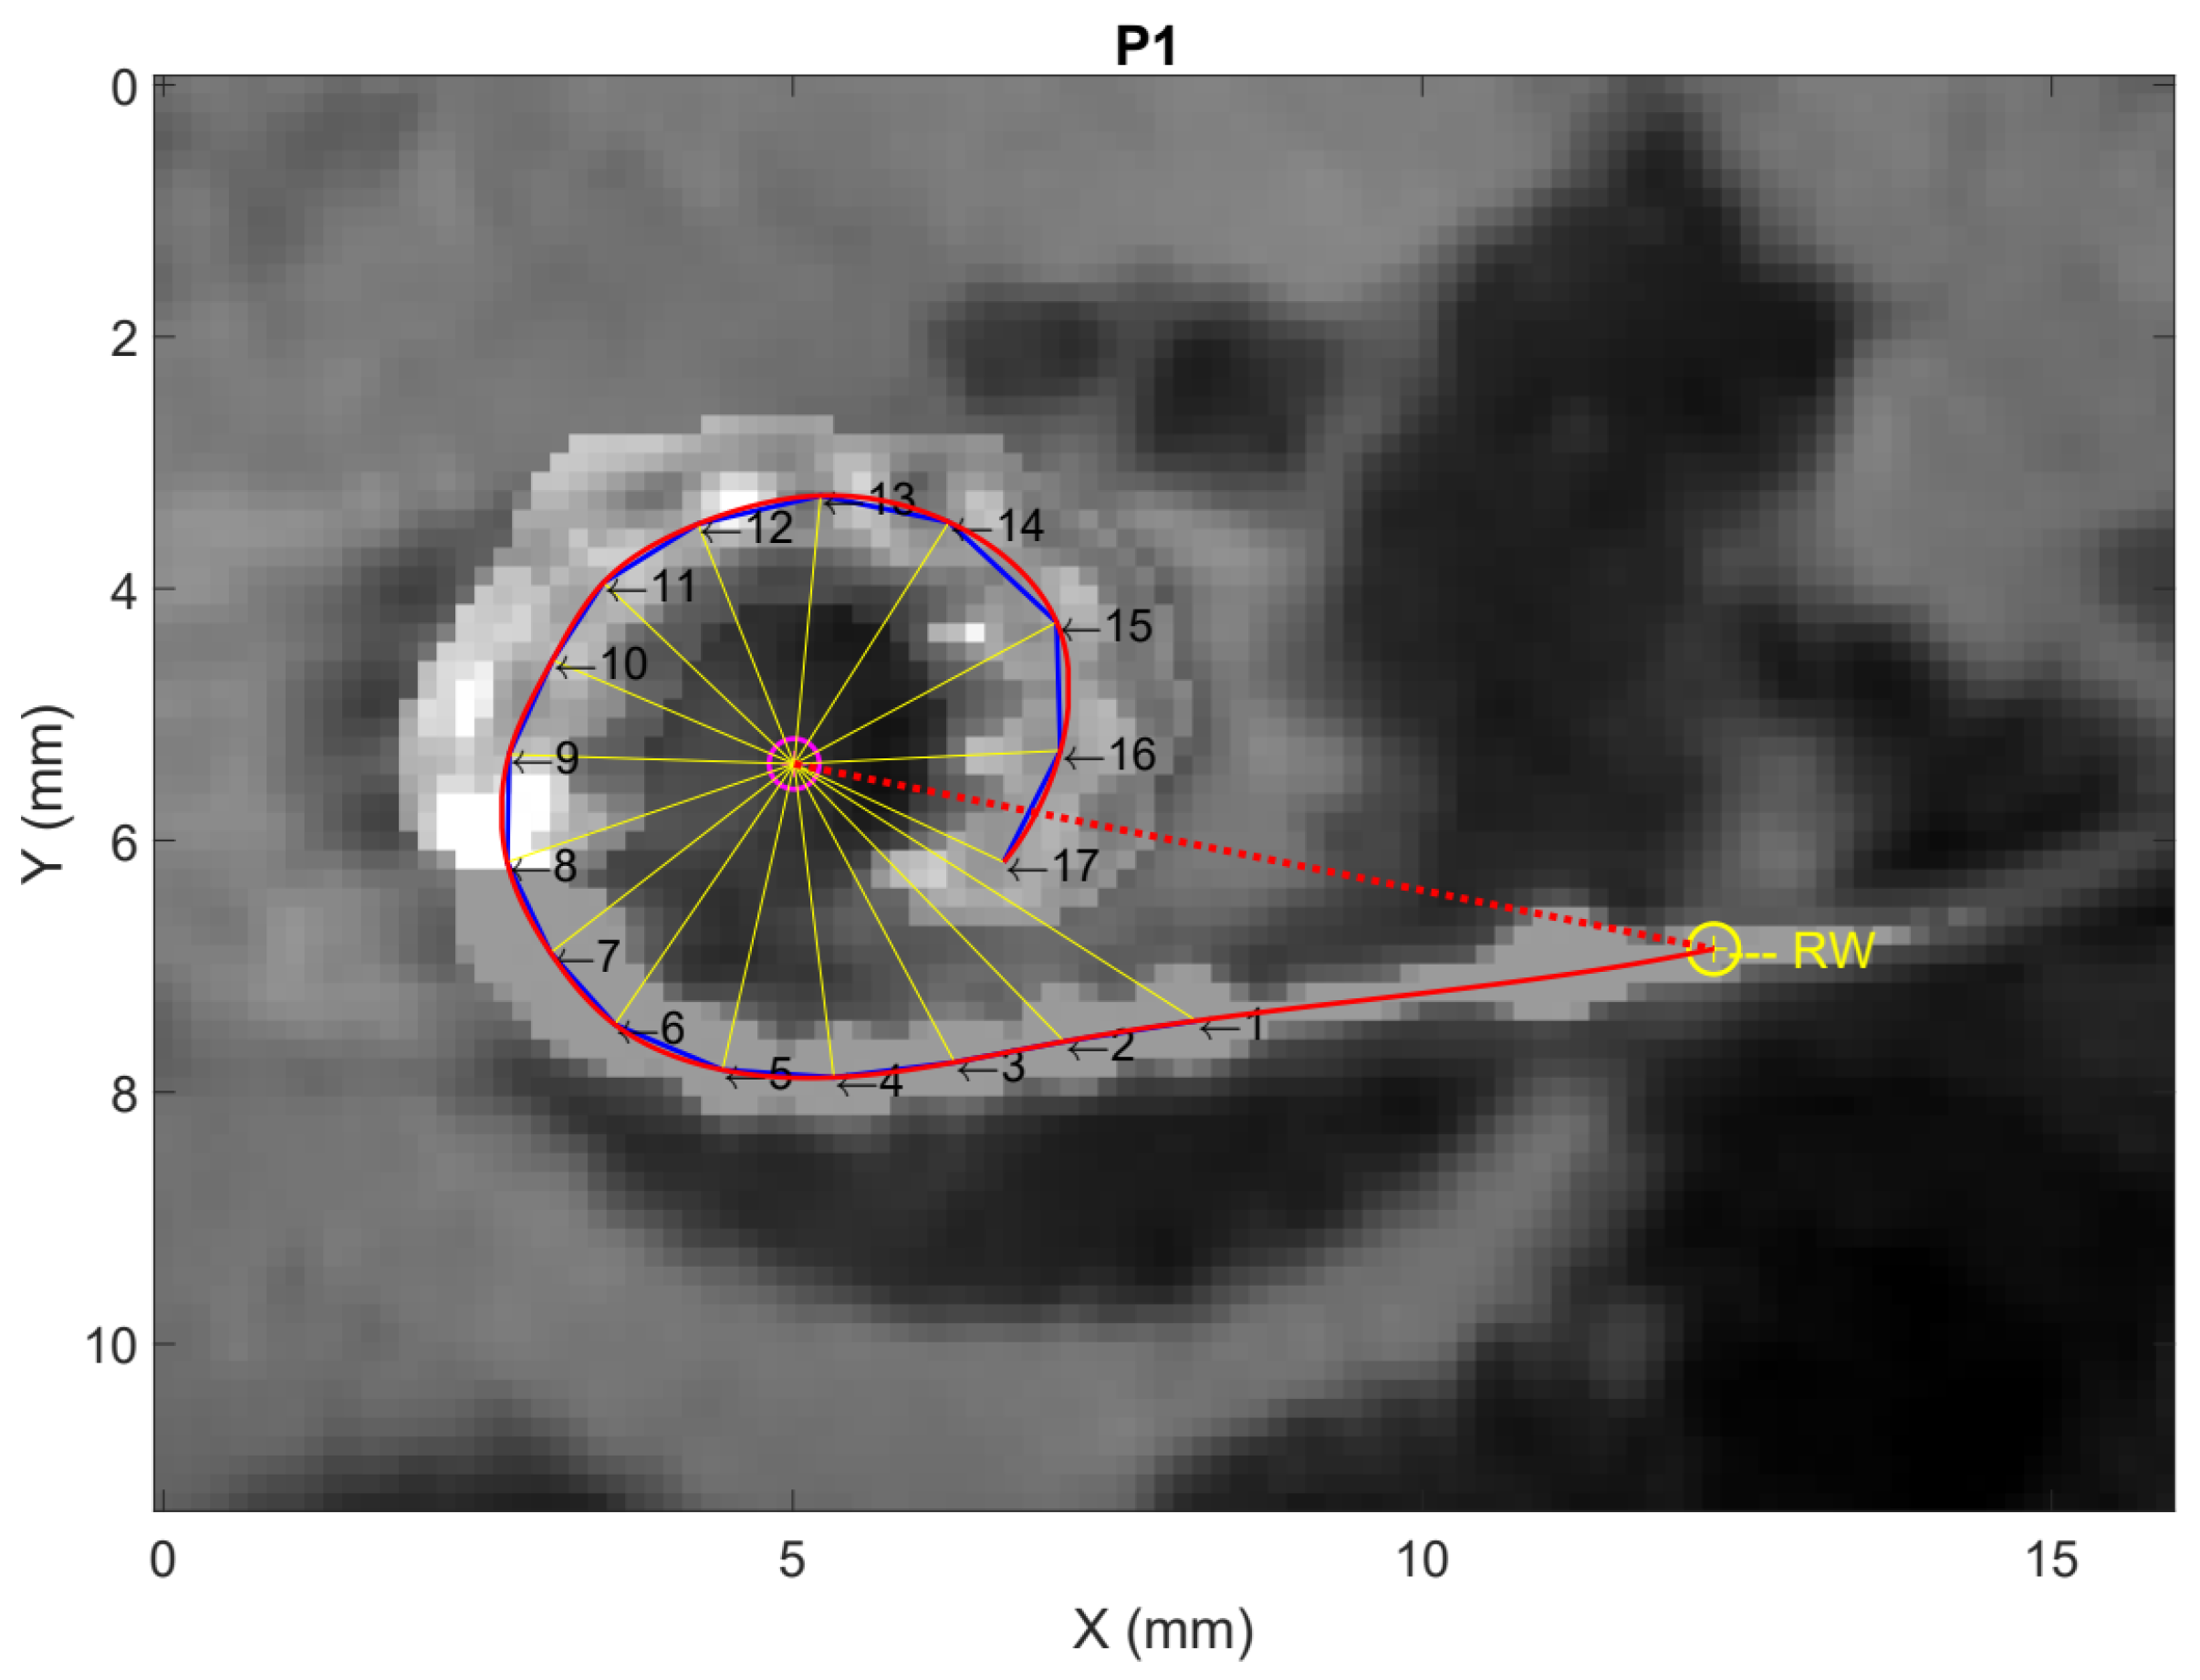

| Participant | Age at Implantation (Years) | Sex | Side | Etiology | Preoperative PTA (dB HL) | Hearing Preservation (%) | Length of Cochlear Duct (mm) | Electrode Array | Angular Insertion Depth (°) |

|---|---|---|---|---|---|---|---|---|---|

| P1 | 65 | Male | Left | Progressive SNHL, unknown cause | 83.75 | 57.1 | 36.2 | HiFocus Mid-Scala (Advanced Bionics) | 374° |